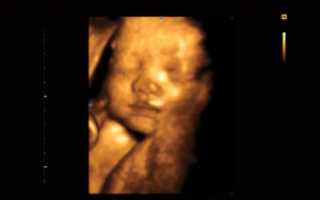

3Д УЗИ делается при беременности с целью детального просмотра частей тела, черт лица плода. При исследовании на экран ультразвукового устройства передается объемное голографическое изображение.

Трехмерное сканирование плода при беременности дает возможность в объемном виде оценить состояние ребенка. Картинка передается на экран аппарата в цветном режиме. Чаще метод используют на втором плановом скрининге, когда четко видны части тела плода.

С помощью 3Д УЗИ делают фотографии и видеозапись движений ребенка в утробе матери. В редких случаях просмотреть малыша не удается из-за того, что он поворачивается спиной. Тогда диагностика проводится через 15–20 минут.

Трехмерное изображение представляется в 3 измерениях — глубине, высоте и ширине. Беременная может увидеть ребенка на экране УЗИ-аппарата в цвете. При этом детально просматривается каждая часть лица и тела, мимика плода.

У него неплохо выражены черты лица. Проводимое 3D-УЗИ в 25 недель позволит увидеть то, как будет выглядеть маленький человек, когда родится. Глаза еще закрыты, брови только начали развиваться, рот сформировался. Продолжает развиваться ушная раковина.

У плода увеличивается вес, он уже составляет около 700 граммов. Малыш может активно шевелить конечностями и сжимать кулачки, сосать пальцы, изучать себя в бессознательном состоянии. Также формируется подкожный слой и генетические черты лица.

У ребенка практически сформировано лицо: развивается нос и щеки, уши смещаются на положенное место, глаза, брови и ресницы приобретают почти окончательный вид.

Все это врач может обнаружить на мониторе, а женщина на фото, которое отдают беременной после исследования. Правда порой для понимания, что где находится, понадобится помощь врача.